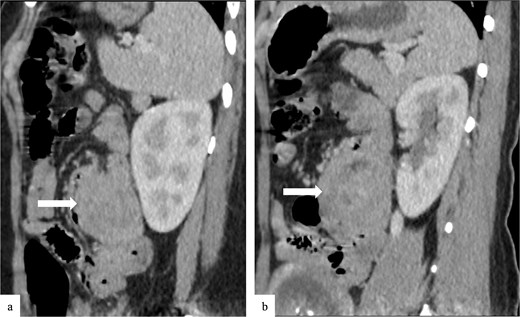

Due to the acute presentation and unavailability of emergency magnetic resonance imaging (MRI), a contrast-enhanced computed tomography (CT) scan of the abdomen was performed with strict fetal protection measures (lead apron, low-dose protocol). The pancreas appeared normal with no signs of inflammation, necrosis, or peripancreatic fluid. Unexpectedly, the scan revealed a duodenojejunal intussusception, likely originating from the fourth portion of the duodenum (D4), involving invagination of a proximal jejunal loop (Fig. 1). A typical pseudokidney sign was observed on sagittal reconstructions (Fig. 2). There was no identifiable lead point such as a mass or polyp. The intussusception was seen tractioning the distal common bile duct, leading to marked extra- and intrahepatic bile duct dilatation (Fig. 3).

Sagittal contrast-enhanced CT images (a, b) showing the duodenojejunal intussusception with a pseudokidney appearance (arrows).